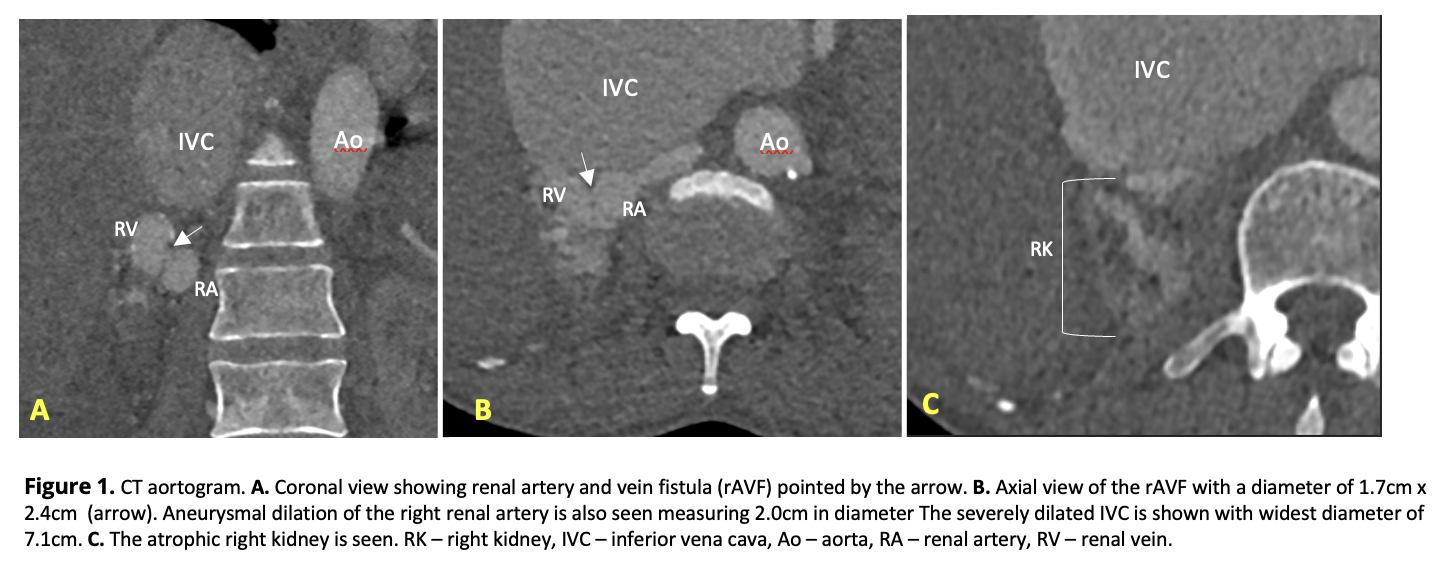

CT aortogram showed an atrophic right kidney with aneurysmal dilation of the distal right renal artery and vein with a fistulous communication in between (1.7x2.4cm, WxAP). The inferior vena cava was severely dilated at 7.1cm. Renal scintigram showed poor right kidney function (6%) and compensatory enlargement of the left (94% function). Echocardiogram showed global hypokinesia, ejection fraction (EF) of 21% with marked dilatation of all chambers and severe pulmonary hypertension (sPAP 48mmHg).

Right renal angiogram revealed a renal artery with an aneurysmal dilatation at its distal segment with a faint opacification of a single fistulous connection to the renal vein, confirming the rAVF seen in the CT aortogram. The fistula measures approximately 3cm in length and 1.7cm in diameter consistent with the CT findings. Based on epidemiology (more commonly acquired than congenital), morphology (single communication, aneurysmal), and chronology of events, the rAVF is considered acquired.